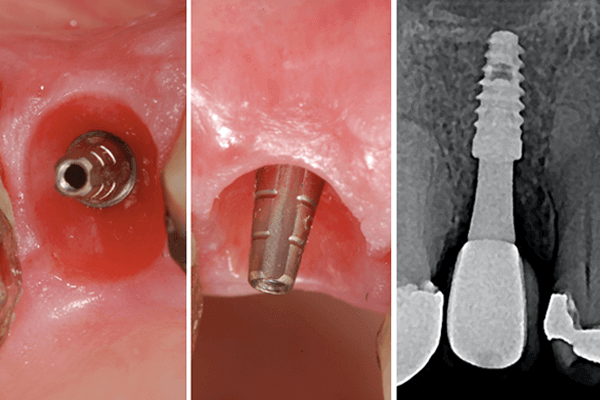

As Figuras 1 a 3 demonstram um caso clínico em que a relação de um pilar protético mais fino com um bom volume de mucosa ceratinizada proporcionou um resultado bastante favorável. O fato do implante ter sido colocado em uma posição mais profunda em relação aos dentes adjacentes foi compensado pela altura e espessura do pilar protético, que respeitou o espaço biológico para acomodar as estruturas dos tecidos moles. As dimensões longa e estreita do pilar deixaram um espaço livre para a gengiva, que proporcionou o tão sonhado selamento biológico peri-implantar.

Desta forma, parece ser razoável acreditar que fatores como o design dos pilares e da supraestrutura protética devem preservar os tecidos moles peri-implantares, proteger o implante e facilitar o acesso para higiene oral dos pacientes. Pilares mais “finos e longos”, especialmente sobre implantes com plataforma cone-morse, melhoram a relação com os tecidos gengivais peri-implantares, mantendo a saúde do conjunto implante-prótese ao longo dos anos.